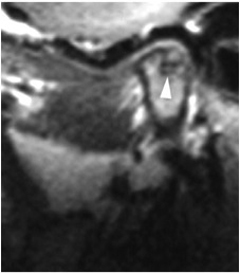

Magnetic Resonance Imaging

This imaging method has become the default “gold standard” for imaging of internal derangements of the temporomandibular joints. Major advantages include the fact that it is non-invasive and does not use ionizing radiation to produce images. It is also able to demonstrate sideways and rotational displacements. It is capable of producing only still images (open and closed), not real-time movement studies, and in that respect it has a significant disadvantage compared to arthrography.

MRI is contraindicated in patients who have been fitted with a pacemaker, have intracranial vascular clips, and metal particles in the eye or other vital structures, due to the strength of the magnetic field. Other contraindications for MRI can include obesity, claustrophobia, or inability to remain motionless for the examination, which can take several minutes to complete.